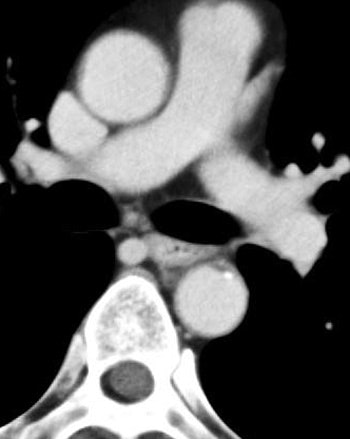

![]() |

| Venous-phase image of a 60-year-old male with stage T1b esophageal cancer. The tumor cannot be seen in the venous phase. |